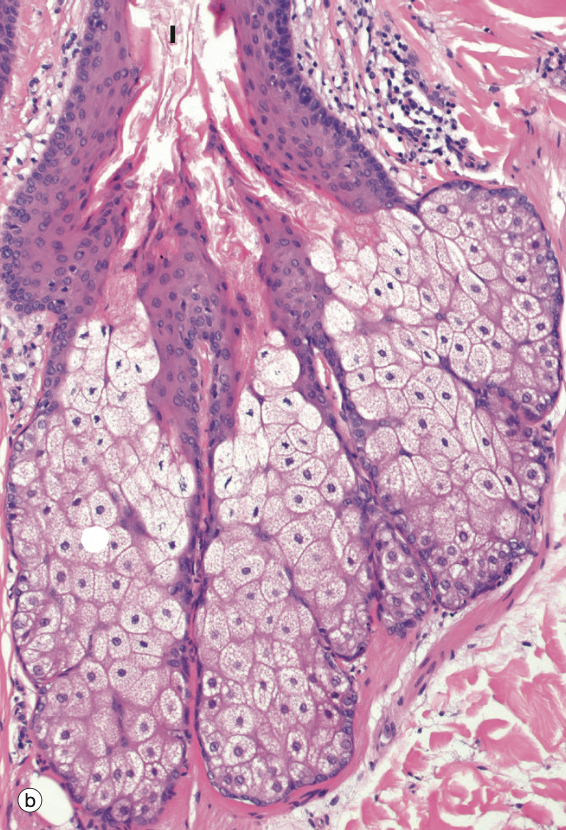

Identify the Structure in the middle

Sebaceous Gland

Identify the Structure on the L and R

Identify the Structure